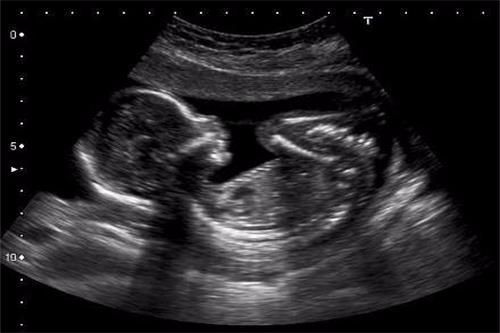

20周第三次产检

检查项目:四维彩超胎儿畸形筛查、复查血常规、尿常规、宫高、腹围、胎心、血压、体重

本次的四维彩超检查主要是看胎儿的头围、腹围、大腿骨长度等是否存在异常。